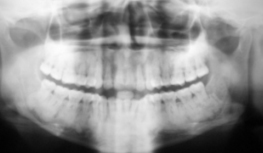

Диагностику проводят с помощью рентгенограммы. Таким образом, можно определить, где в полости рта есть плотные новообразования с мелкими кальцинатами. После того как заболевание будет выявлено, специалисты назначат лечение, опираясь на знания о тех или иных разновидностях. В дальнейшем и лечение будут проводить на современном оборудовании, с использованием препаратов последнего поколения. Основа лечение – резекция дефектной области челюсти. Далее надо удалить опухоль частично, сохранив целостность ткани кости. Однократного удаления достаточно для лечения заболевания.